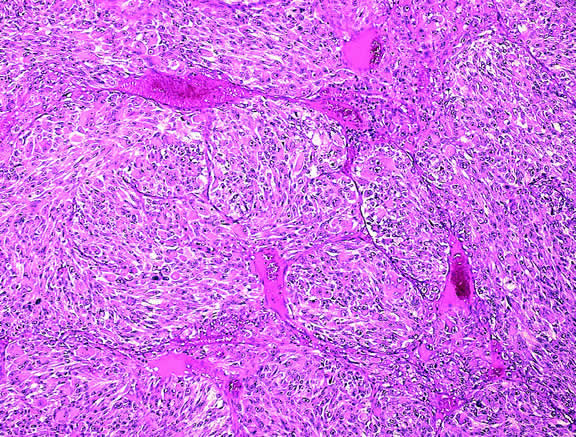

MICROVASCULAR PATTERNS.

Certain microvascular patterns within uveal melanomas have been shown to be prognostic indicators for death from metastatic melanoma.121 Folberg and associates identified nine morphologic patterns of tumor vessels in eyes removed for ciliary body or choroidal melanoma and designated them: (1) normal, (2) silent, (3) straight, (4) parallel, (5) parallel with cross-linking, (6) arcs, (7) arcs with branching, (8) loops, and (9) networks. The presence of vascular loops and microvascular networks composed of back-to-back loops that encircle microdomains of tumor are strongly associated with death from metastatic melanoma122 (Fig. 45). Prognostic vascular patterns appear to be consistent throughout the depth of a tumor, and the cross-sectional area occupied by prognostic microvascular patterns also has prognostic value.123,124 Additional studies from Folberg's laboratory have compared the microcirculation architecture of nevi and melanomas125 and examined the relationship between microvascular architecture and the aggressive behavior of ciliary body melanomas.126 Attempts to detect prognostically significant microcirculatory patterns in vivo using noninvasive imaging techniques including ultrasonography127,128 and confocal angiography with fluorescein or indocyanine green have been made.129,130 A study of 496 posterior uveal melanomas at the AFIP confirmed that the presence of loops did indicate poor outcome but was not as good a prognostic indicator as the mean diameter of the largest nucleoli, cell type, or tumor size.131

Fig. 45. Networks of vascular loops, uveal melanoma. Fibrovascular septa divide parts of this predominantly epithelioid melanoma into roughly circular zones called vascular loops. Vascular networks are composed of adjacent vascular loops. Uveal melanomas that contain vascular loops and networks have a poorer prognosis. (Hematoxylin-eosin, × 50.)